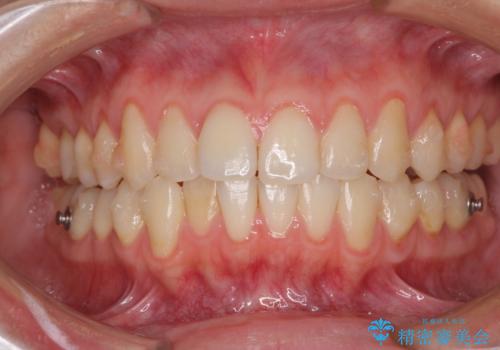

- 矯正装置

- インビザライン

- 治療期間

- 11ヶ月

1日22時間の装着時間をしっかり守ってくださったので、予定していた1年よりも早く治療を終えることができました。

インビザライン矯正特有の奥歯がしっかりと咬合しない感覚も改善され、大変満足していただきました。